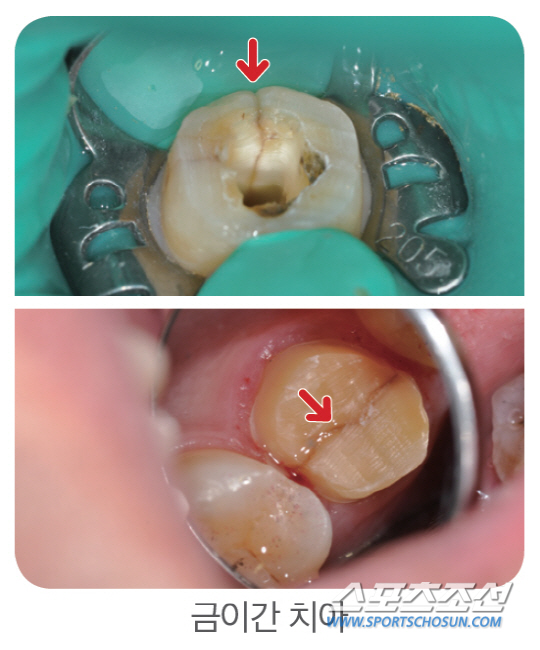

치아에 금(crack)이 간 초기에는 통증이 있다없다를 반복하기 때문에 병원을 찾지 않는 사람들이 많다. 하지만 금이 상당히 진행돼 통증을 참을 수 없게 돼서 병원을 찾으면 이미 치근(치아의 뿌리)까지 손상돼 발치를 해야 하는 경우가 발생할 수 있다.

치아균열증후군의 대표적 증상은 씹을 때 예리한 통증을 느끼는 것인데 금이 간 곳이 더욱 벌어져 신경까지 자극이 가해질 때 나타난다. 금이 생긴 초기에는 시큰거리거나 찌릿한 증상이 가끔 있어 방치하는 경우가 많다.

이진규 강동경희대 치과병원 보존과 교수는 "시큰거리고 찌릿한 통증을 오래 방치하면 치근까지 금이 진행돼 발치를 해야 하는 경우가 생긴다"며 "치아의 금이 더 깊게 진행되기 전에 조기 치료하는 것이 중요하고, 생활습관 개선을 통한 예방이 최선"이라고 조언했다.